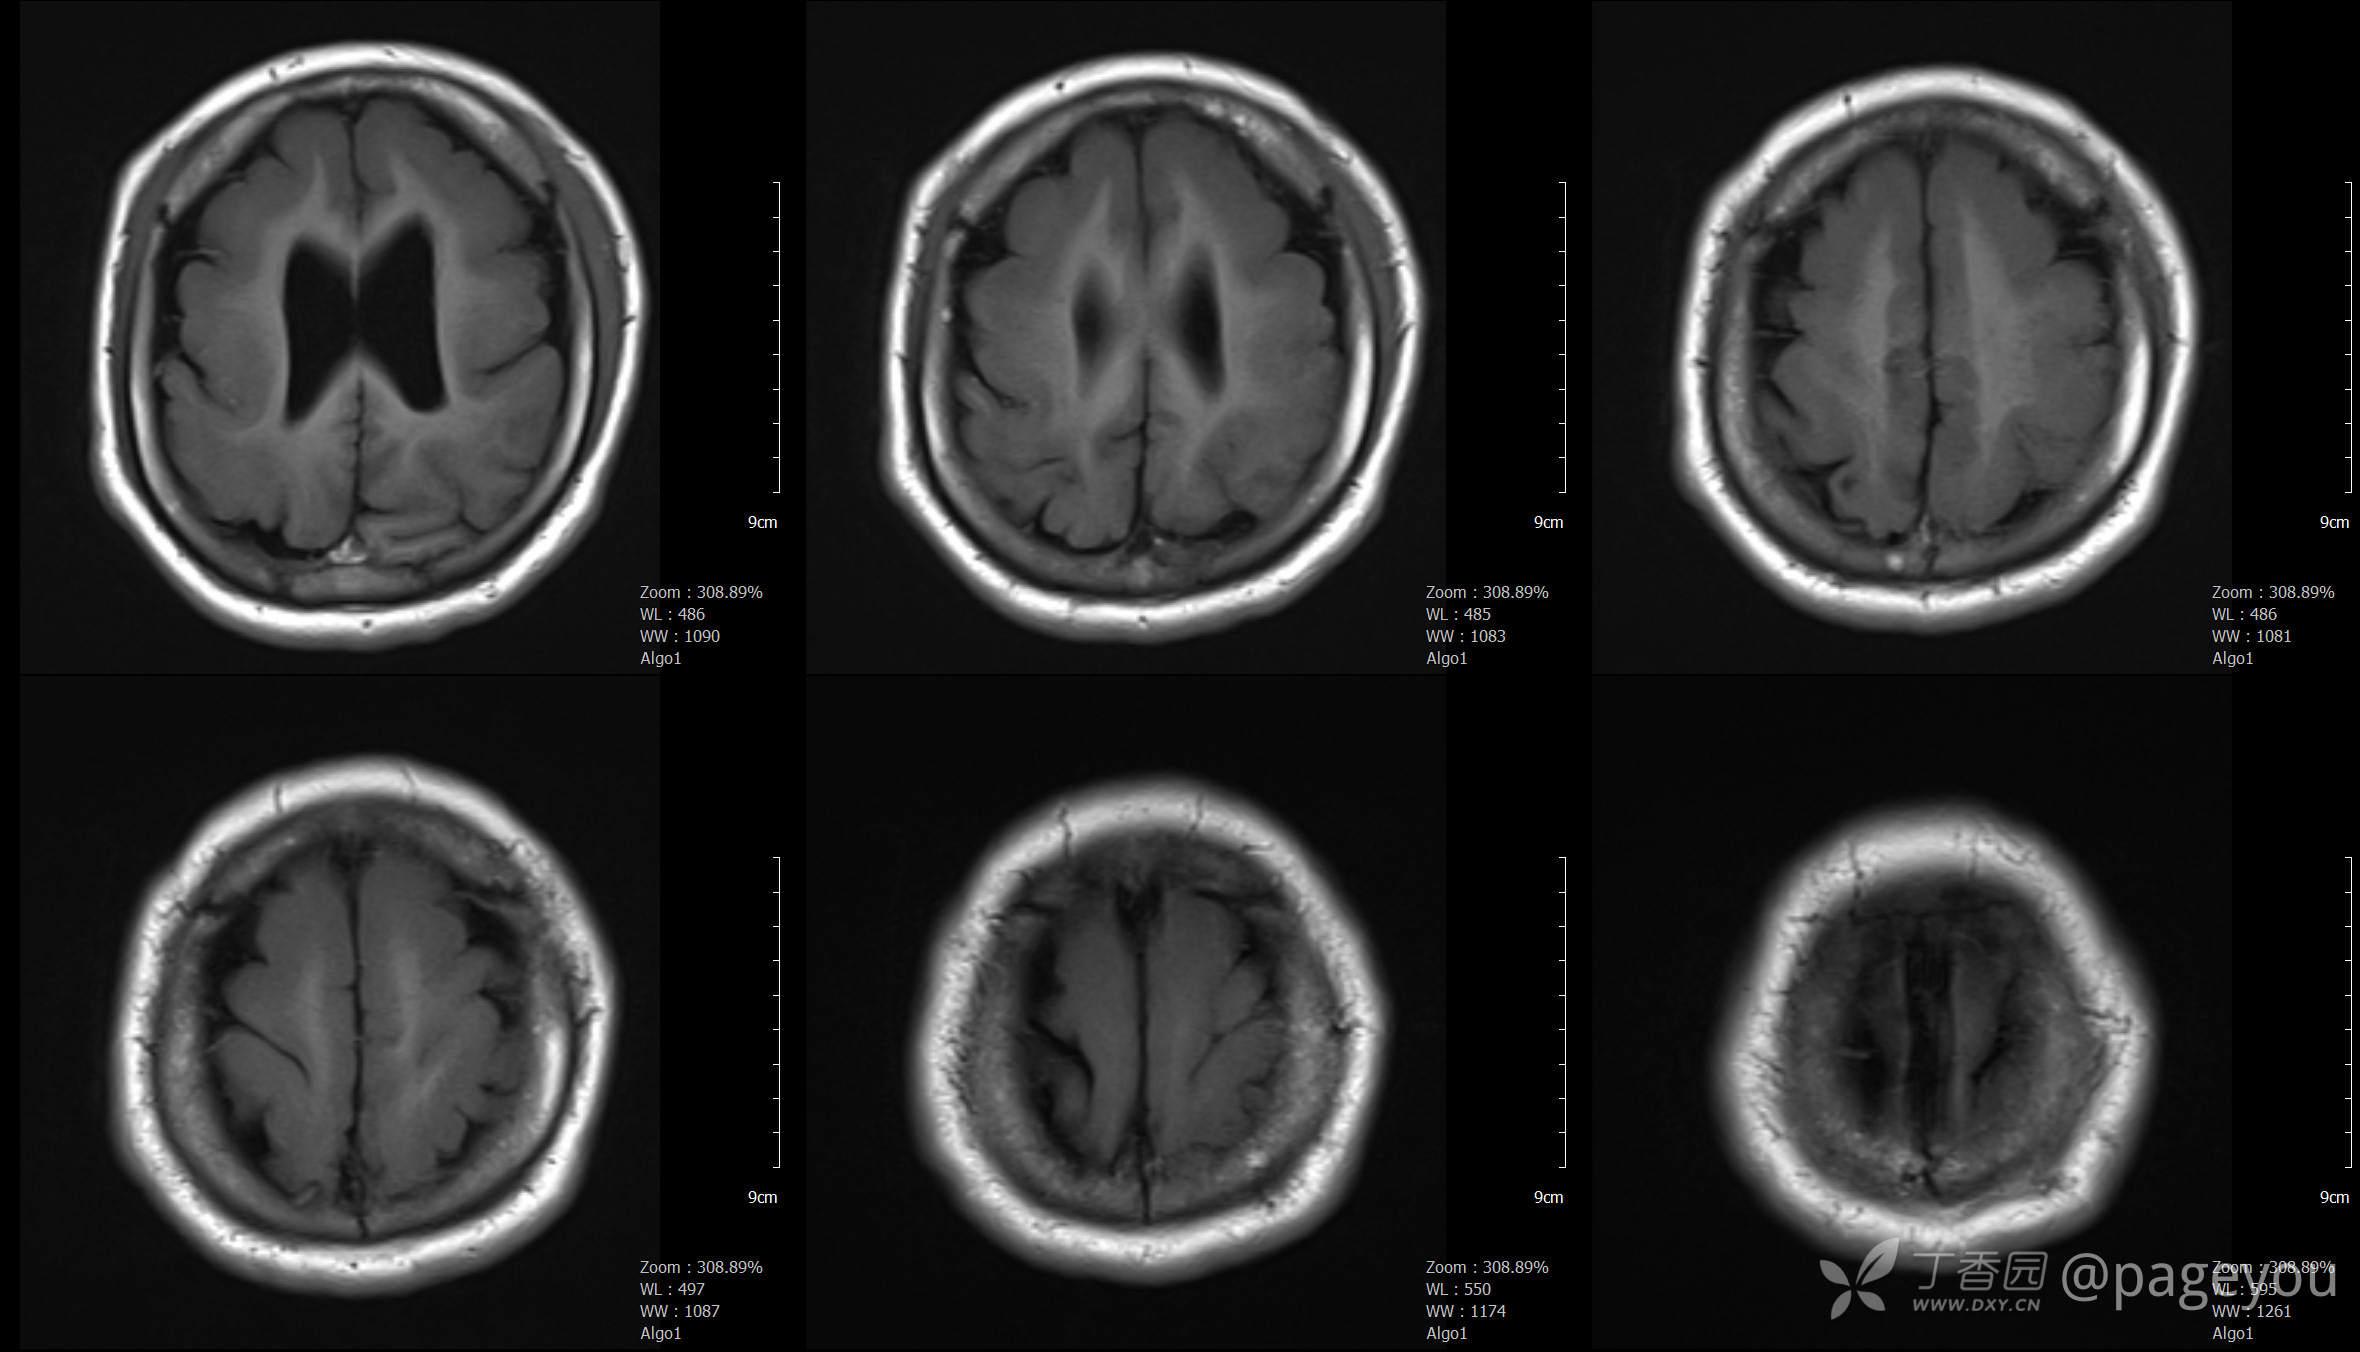

头颅CT:

头颅MRI: